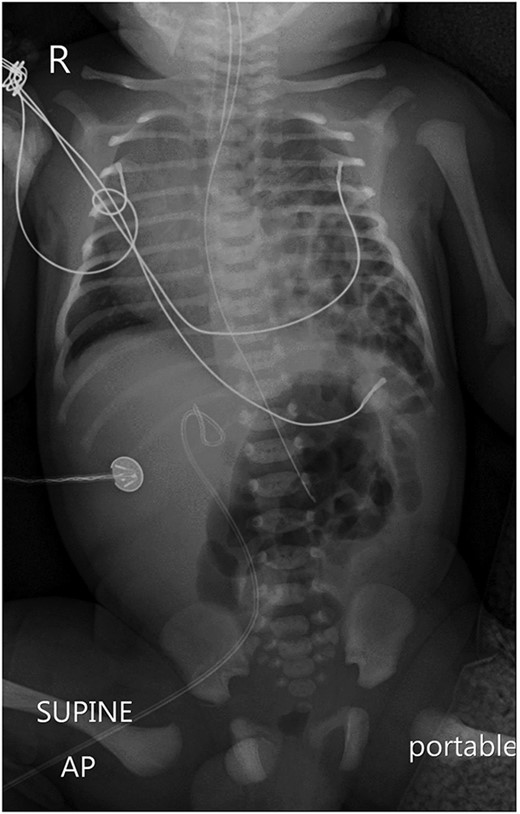

A chest X-ray revealed a left-sided diaphragmatic herniation of bowel loops into the left hemithorax along with displacement of the cardiac shadow to the right (Fig. 1). Nasogastric and endotracheal tubes were also inserted. Umbilical arterial and venous catheter insertion was attempted but failed and removed the next day.

A portable X-ray photo of the chest, abdomen and pelvis shows the right mediastinal shift, total collapse of the left lung, partial collapse of the right lung and air-filled structures (bowel loops) extending from the abdomen into the chest.